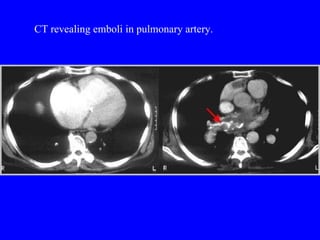

Pulmonary embolism (PE) is a common and potentially fatal condition where blood clots block arteries in the lungs. An estimated 5 million venous thromboses occur annually worldwide, with 10-30% of PE cases correctly diagnosed. Risk factors include older age, cancer, obesity, surgery, trauma, and genetic or acquired hypercoagulable states. Diagnosis involves assessing clinical probability based on symptoms and risk factors, then confirming with tests like D-dimer, chest imaging, ventilation-perfusion scanning, pulmonary angiography, or CT pulmonary angiography. Treatment focuses on anticoagulation to prevent further clotting while allowing natural lysis of existing thrombi.